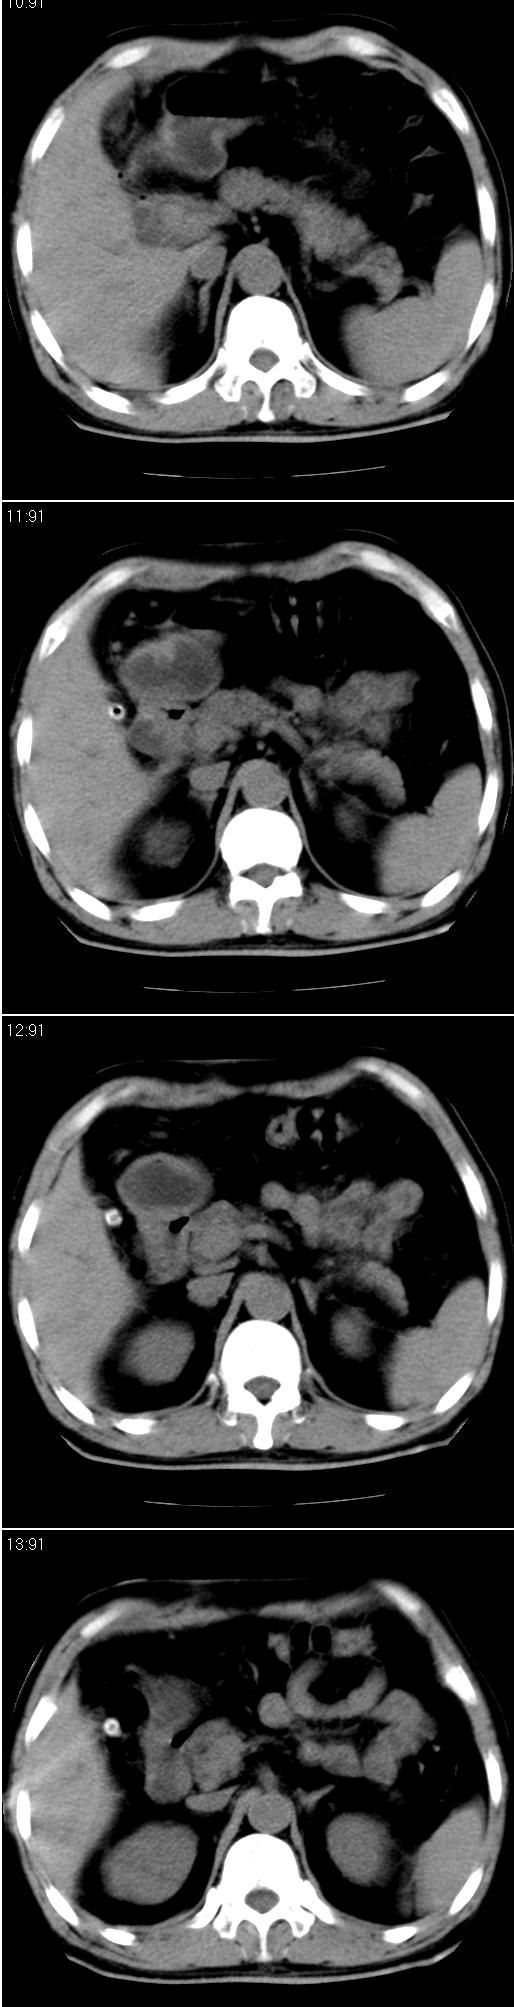

男,57岁。因胆结石阻塞性黄疸入院。这是胆囊切除术后的照片,看看此片到底有什么问题。

胆总管有没有问题,尤其是肝门附近的胆总管?

肝内外胆管轻度扩张,胆囊窝内见引流管考虑胆囊切除术后改变.胃窦部软组织似增厚,建议胃镜检查.

在手术切除胆囊的过程中,发现肝门部胆总管恶性占位,因为家属不同意手术,没有切除,能看出来么?

现有资料很难说,薄层可能清楚些,如临床不提供,易诊断为术后改变。

肝内外胆管轻度扩张。楼主提示左右肝管合汇区域壁稍厚。胆总管末段壁似也稍厚有轻度强化。就现有资料诊断难。